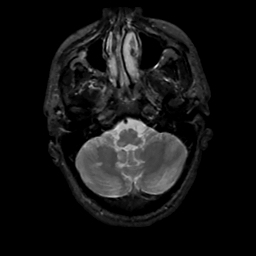

MR Study #1, February 10, 1991 -- Slice #9

[Home][Help][Clinical][Tour 1][Tour 2] Slice 9